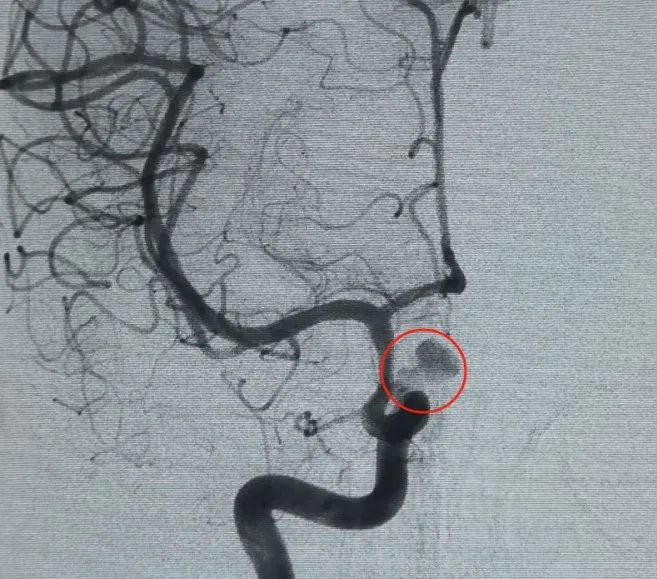

Dostęp naczyniowy ustalono poprzez nakłucie tętnicy udowej i Perdenser®Cewka 3D o wymiarach 6mm × 20 cm została po raz pierwszy rozmieszczona w celu utworzenia kosza, uzyskując stabilną apozycję ściany i zapewniając bezpieczne podparcie wewnątrzskarbowe. Następnie wstawiono Perdenser®Cewka 3D 6mm × 15 cm, aby zakłócić przepływ krwi w płatowym worku potomnym.

Perfiller®Cewka ekspansywna 3mm × 6 cm i Perfiller®Następnie umieszczono rozszerzalną cewkę o wymiarach 3mm × 2 cm, aby zakończyć okluzję szyjki. Następnie Nuva®Flow Diverter (TJED-D-5.0-16) został dostarczony i rozmieszczony w poprzek szyi tętniaka. Dalsza angiografia zarówno w widoku przednio-tylnym, jak i bocznym potwierdziła doskonałe pokrycie, dobre położenie ściany i wyraźną przezroczystość promieniową, z wyraźną stagnacją kontrastu.